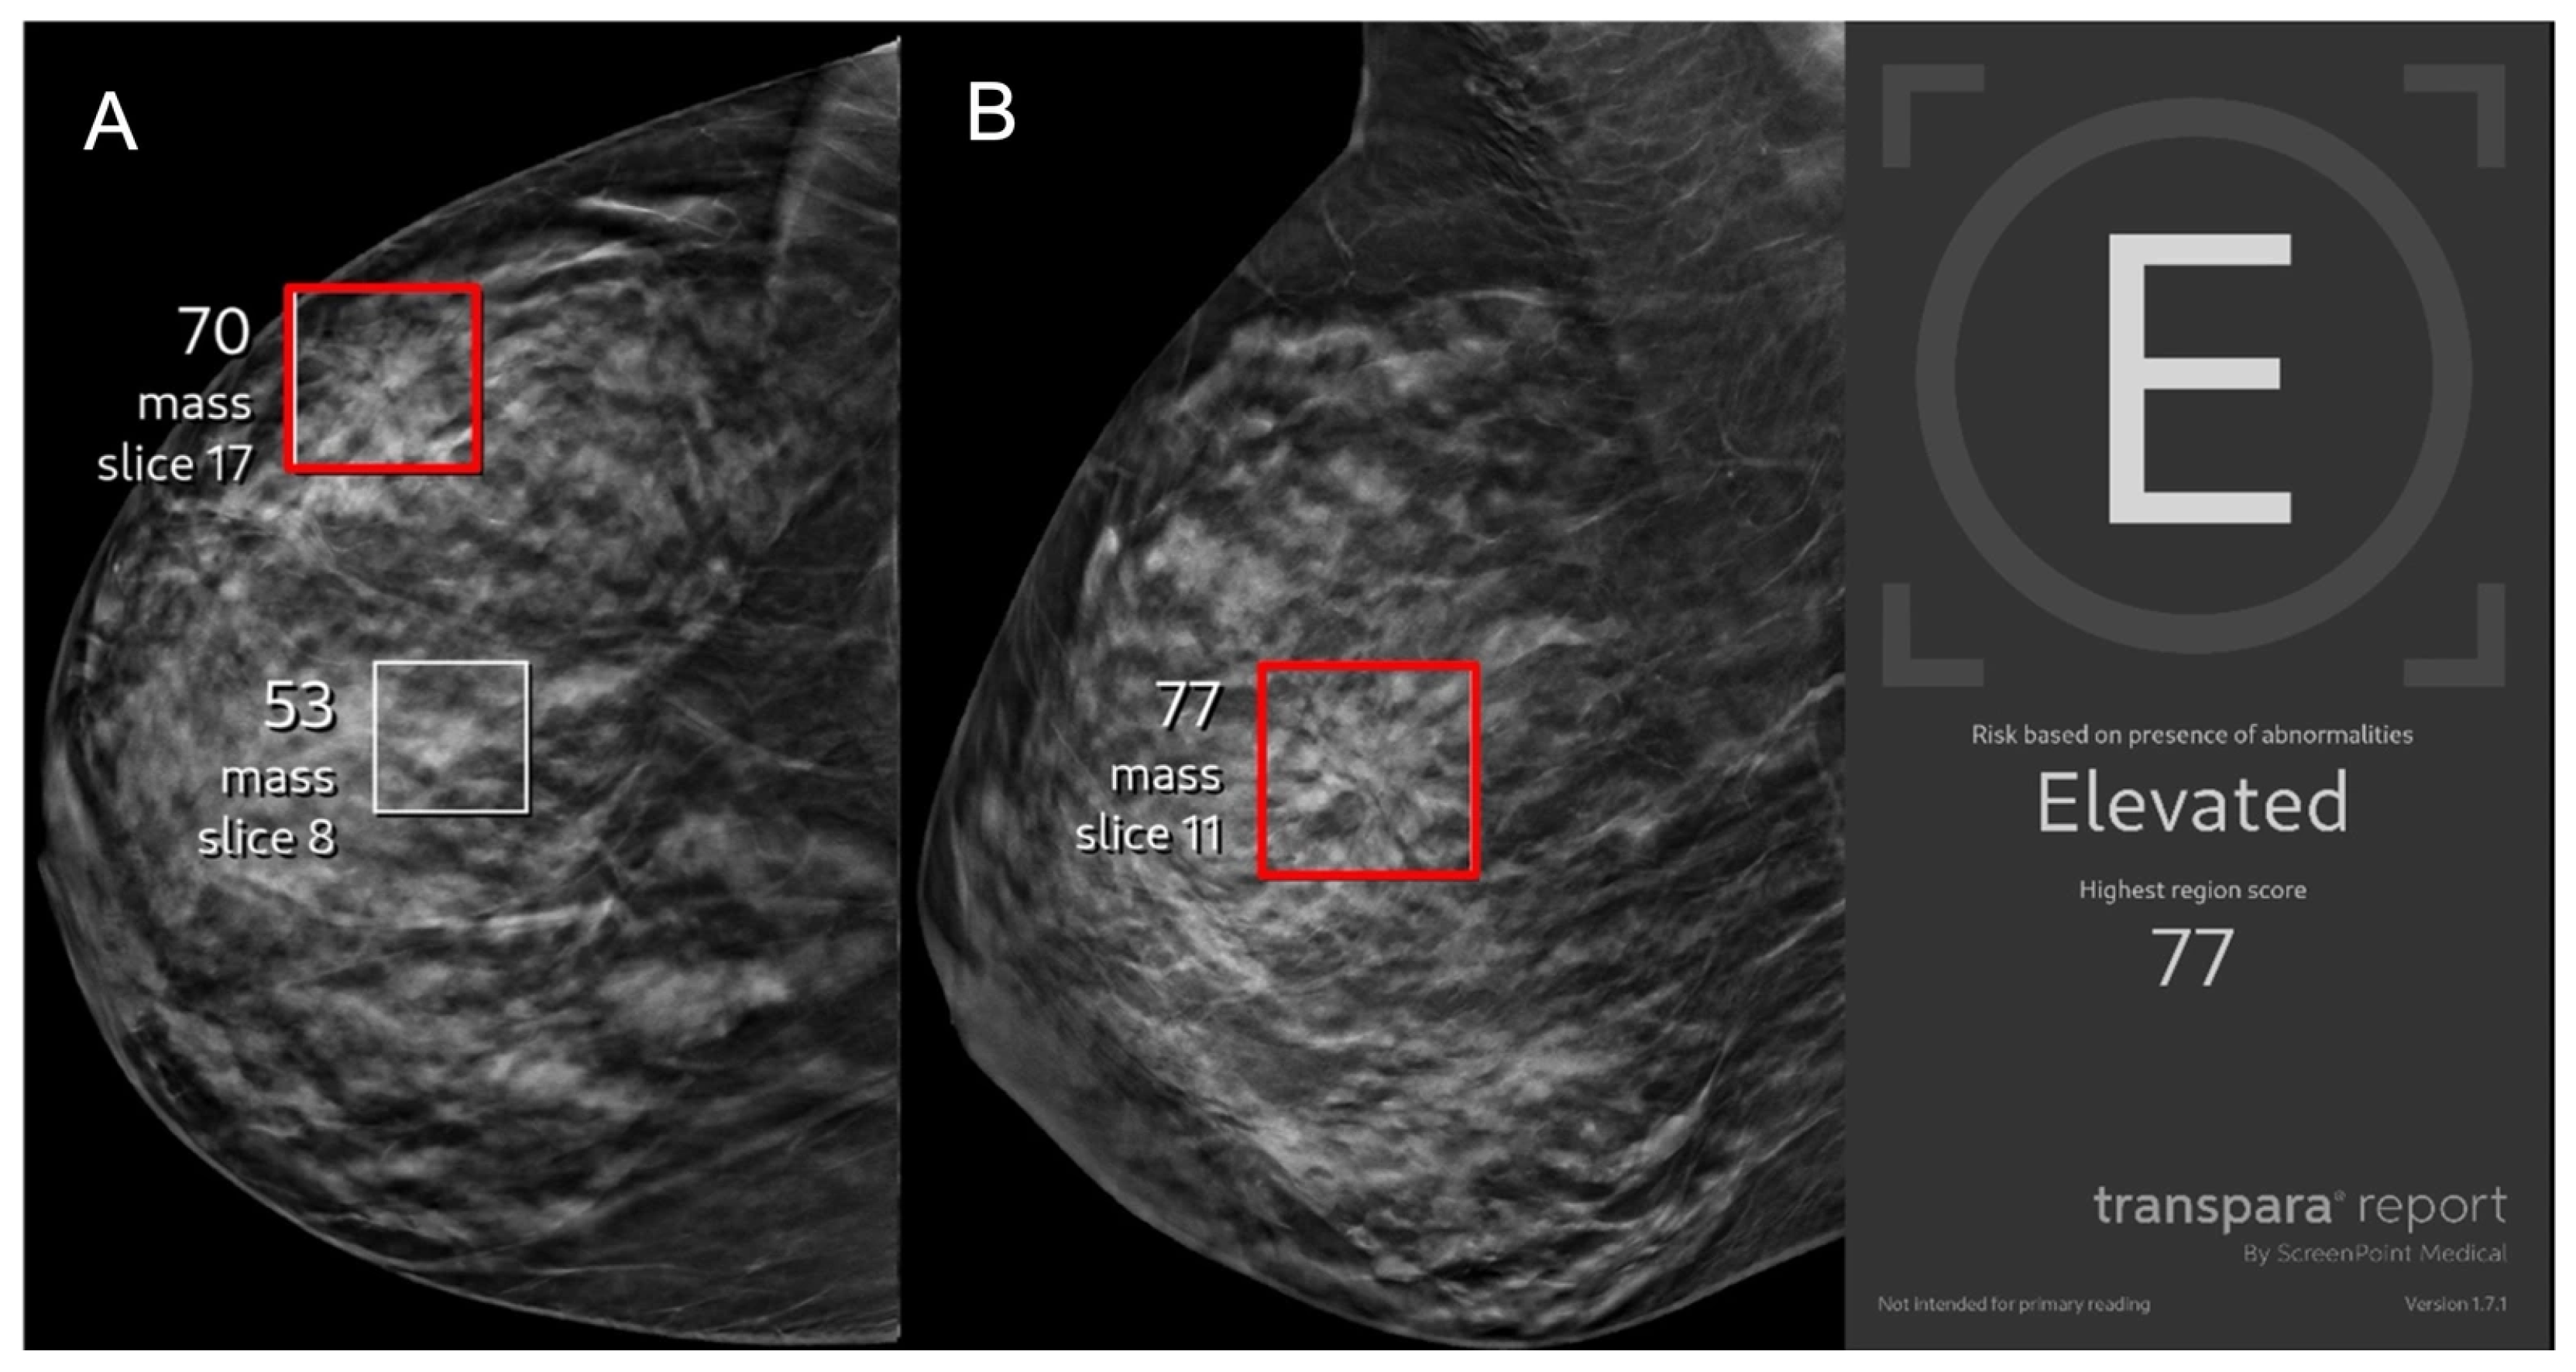

Performance of an Artificial Intelligence Support System on Screening Mammography Cases Proceeding to Stereotactic Biopsy